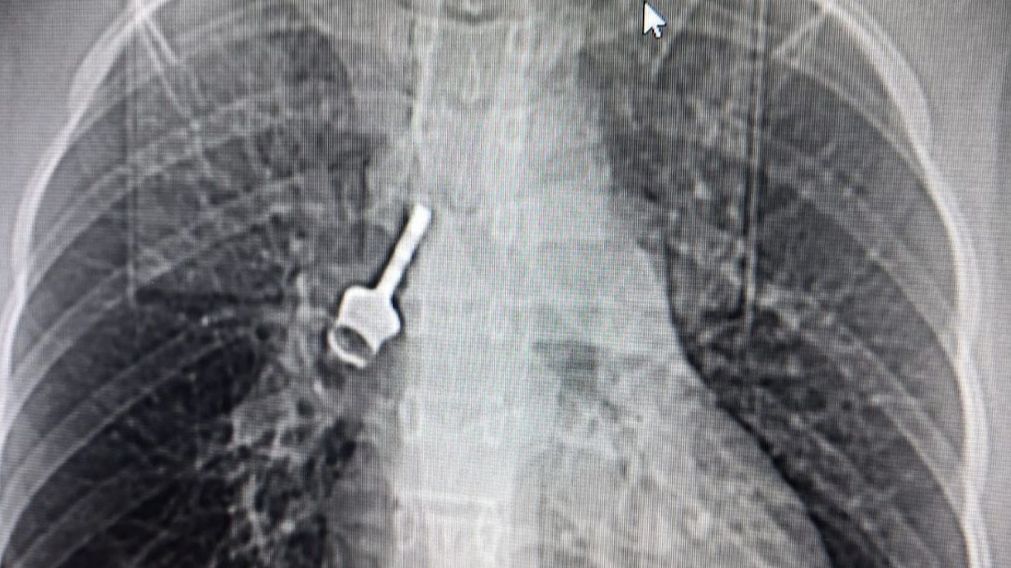

Salvar a una niña del Congo que tenía una llave en el pulmón, un nuevo éxito del ‘doctor de los récords’

Allí se encontró a una niña que llevaba dos años con una llave alojada en el pulmón derecho

El médico coruñés Diego González Rivas, conocido como el ‘doctor de los récords’ o el ‘Willy Fog de la cirugía’, todavía se muestra sorprendido por el hecho de que la niña consiguiese sobrevivir a algo así. “Es un caso único. Dos años con un elemento tan grande en el pulmón. Que haya sobrevivido a eso es sorprendente”, cuenta a NIUS.

Cuenta que la niña tenía 12 años cuando se tragó la llave. “Ante algo así, lo más probable es que se hubiese muerto. Pero tuvo la suerte de que el objeto no se le quedó atascado en la tráquea. Siguió bajando hasta el pulmón principal”, explica.

Un caso que se habría operado de urgencia en España, no encontró una solución en el Congo. “Tenía tos crónica y se fatigaba con el mínimo esfuerzo. Casi no podía ni respirar. No podía vivir con eso así”, cuenta el doctor.

Y así lo hizo. Con su técnica pionera, Uniportal Vats, consiguieron extraerle la llave con una incisión de solo tres centímetros. “Hicimos broncotomía. Le abrimos el bronquio, le quitamos la llave, y luego se lo reconstruimos”, cuenta. Al día siguiente, la niña ya caminaba por el hospital.